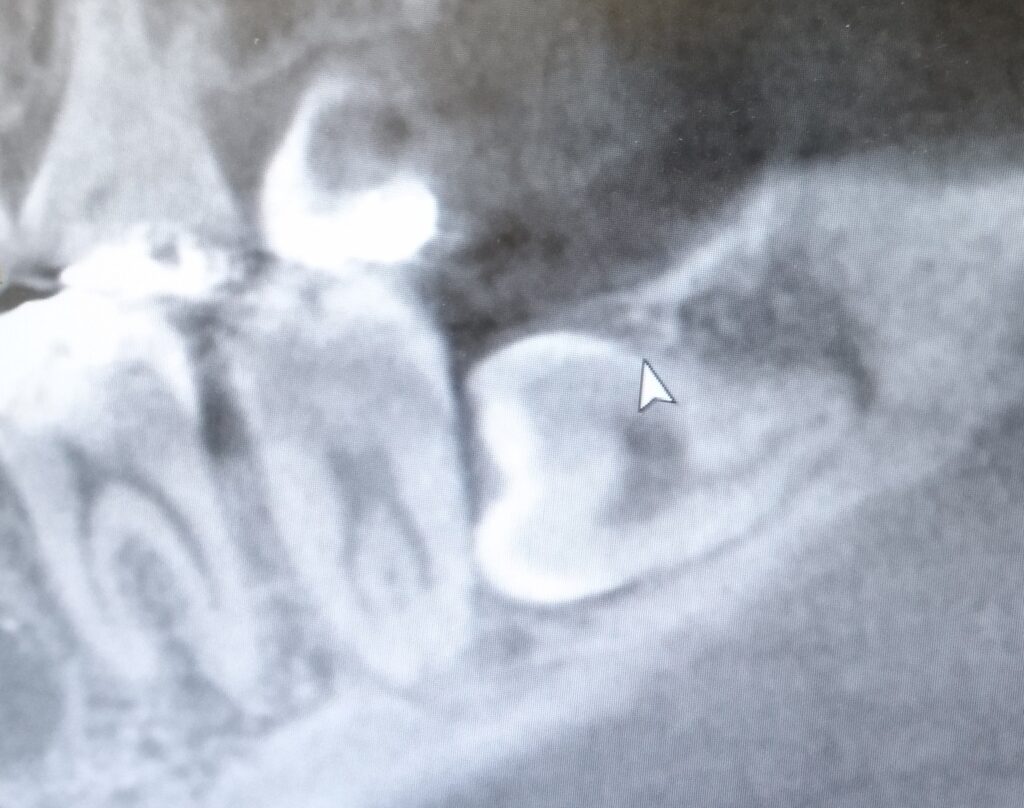

斜めに埋まった親知らずのレントゲン写真

親知らずの抜歯や腫瘍の摘出などの口腔外科処置には少なからずリスクも伴います。当院では口腔外科で研鑽を積んだ歯科医師も在籍し、安全かつ患者様に負担が少なくなるよう治療に取り組みます。一方で当院には入院設備はないため、入念な診査を行い当院だけでの治療は困難と判断した場合は、大きな病院の専門医に紹介いたします。